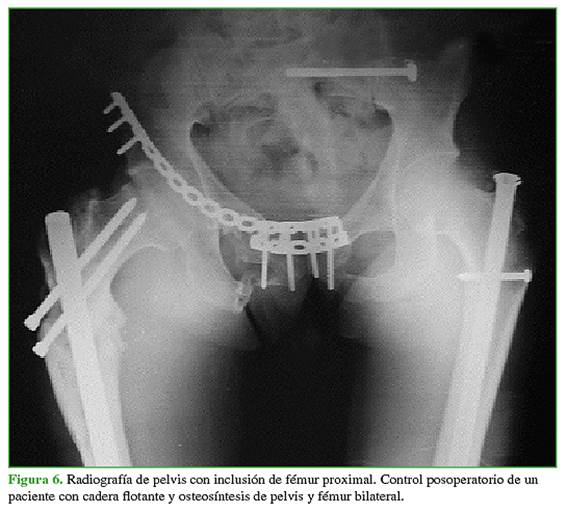

La fractura de fémur había sido tratada con clavos endomedulares en el 95,7% (n = 22) (Figura 6) y con placa y tornillos solo en el 4,3% (n = 1). La mediana de días de internación de esta población fue de 8 (rango 5-10). La mediana de la duración de los procedimientos fue de 247 min (rango 120-480) y la mediana de la pérdida hemática estimada durante la operación, de 500 ml (rango 300- 900).

La mediana de los procedimientos traumatológicos realizados por paciente fue de 5 (rango 4-5). La mediana del tiempo de espera para la resolución total de la CF fue de 12 días (rango 2-54) principalmente demorado por el estado clínico-hemodinámico del paciente. En el momento del alta, 17 (73,9%) pacientes no tenían dolor y dos (8,8%) presentaban una lesión del nervio ciático poplíteo externo, que remitió por completo en ambos casos, a los seis y ocho meses de la cirugía. El 56,5% (n = 13) sufrió lesiones asociadas (Tabla 2).